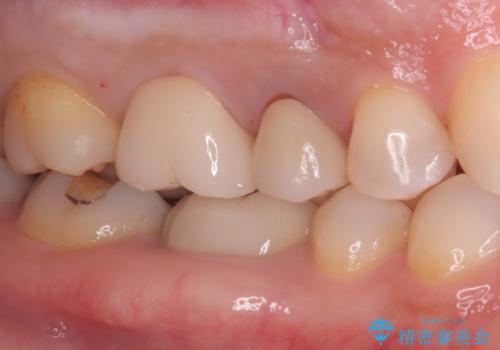

- 長年使用してきた奥歯の古い銀歯のやりかえを主訴にご来院されました。診査の結果、銀歯の下の歯質が薄くなっている部分があり、今後強い力が加わると歯が割れてしまう(破折)リスクが高いと判明しました。このリスクを回避し、歯を長期的に守るため、歯全体をしっかり覆う**セラミッククラウン(被せ物)**による修復を提案。機能的な強度と自然な見た目の両立を目指しました。

治療では、まず古い銀歯を慎重に取り外し、内部の虫歯の有無を確認しました。その後、残っている歯質を保護し、強度を高めるために、適合性に優れたオールセラミッククラウンを作製・装着しました。